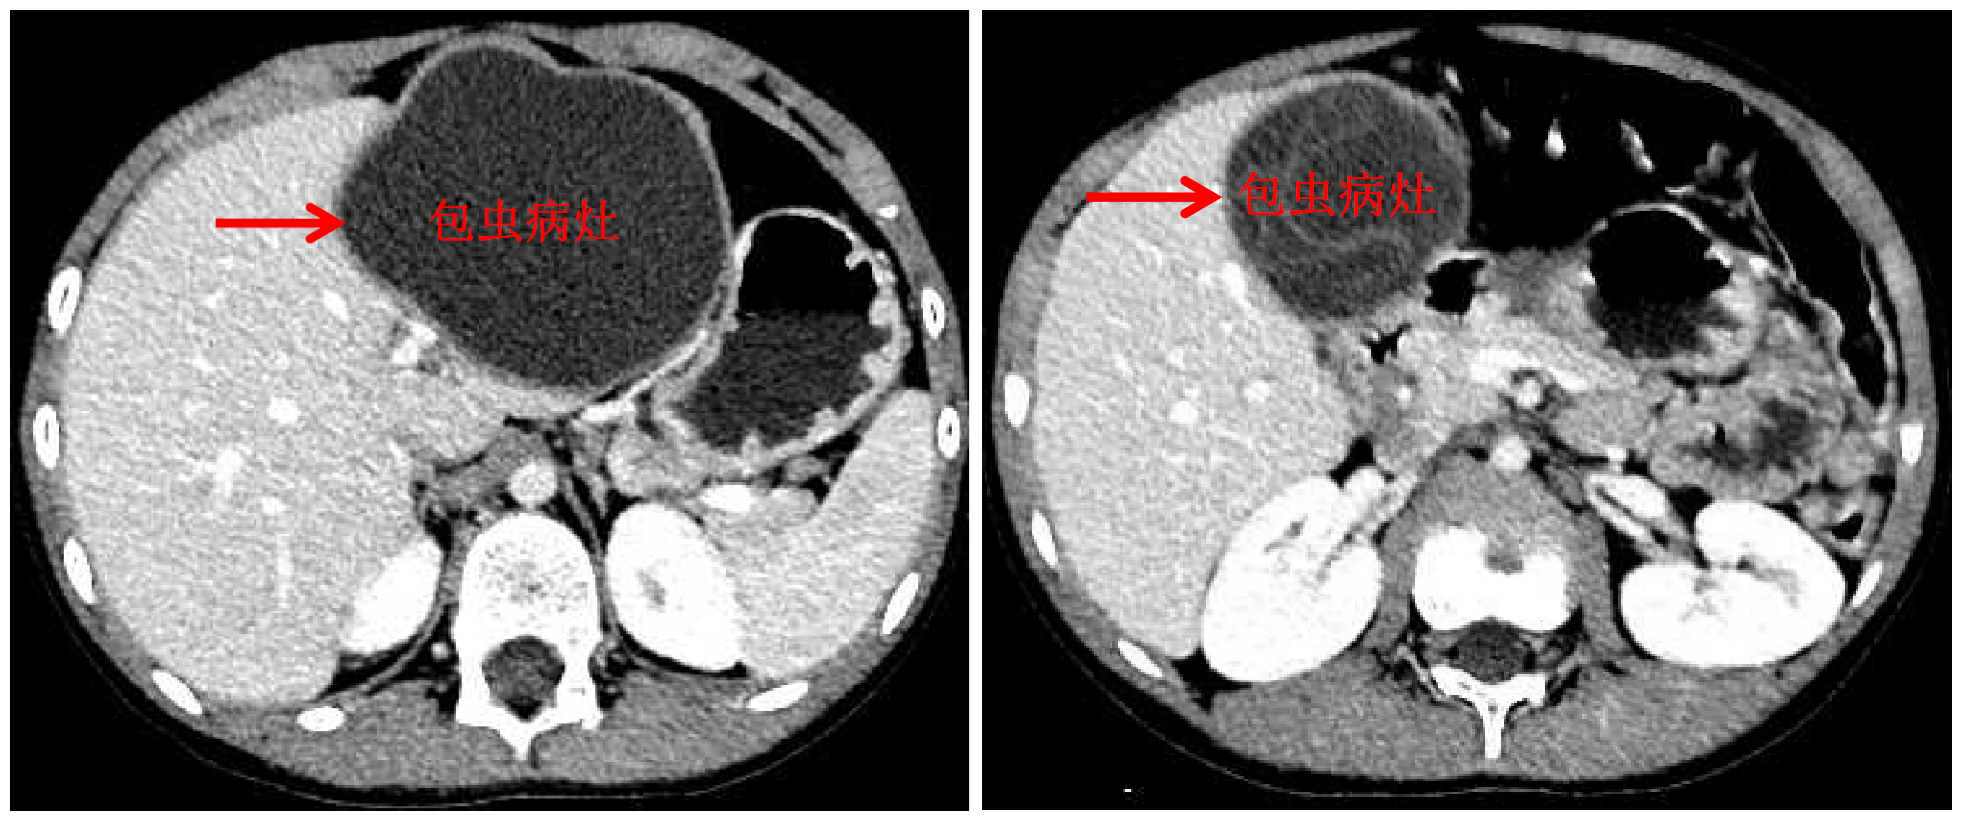

华体会娱乐(中国)网10月13日电 国庆前,8岁的小扎西被父亲带到了西藏大学附属拉萨市人民医院普外科,此次距离孩子确诊肝包虫病已有一年之久。腹部影像显示,小扎西体内的囊型肝包虫病已经侵袭了左肝大部。

面对肝包虫病患儿,华体会娱乐平台附属北京清华长庚医院肝胆胰外科援藏医生、现任拉萨市人民医院普外科主任王学栋已经历过丰富的历练——由董家鸿院士带领的清华长庚肝胆胰团队常年深入青海、四川等游牧地区义诊,为终末期肝包虫病患者提供治疗。但对于小扎西,无疑开腹摘除术是更加简单、安全的方法,而腹腔镜下切除病灶,能达成藏族同胞对微创的要求,却是困难重重——病灶巨大,腔镜下解剖及显露肝门困难,且病灶紧贴肝中静脉,保留肝中静脉较困难。

包虫病灶